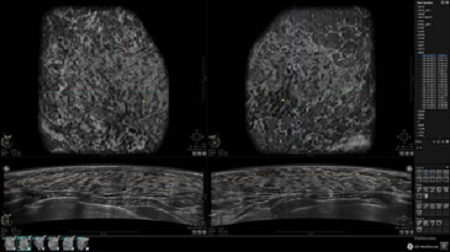

GE INVENIA ABUS – это современный УЗИ аппарат, который создан для точной и эффективной диагностики сканирования с высокой плотностью молочных желез. Выявляемость патологий раковых и предраковых стадий заболевания составляет 55%, что в конечном счете позволяет ставить врачу точные и своевременные диагнозы. Традиционные методы использования маммографии не показывают такой выявляемости, ограничиваясь лишь 3-38%.

УЗИ-аппарат GE INVENIA ABUS позволяет проводить максимально операторонезависимые процедуры, что значительно снижает риск неправильной постановки диагноза и сопутствующие издержки на обработку информации. Система готовит отчет в течение 3-х минут после сканирования, это безусловное преимущество по сравнению с обычным УЗИ сканером.

• датчик с изогнутой апертурой для качественного исследования

• сканирование одной грудной железы в трех проекциях не более 60 сек.;

• обработка результатов за три минуты.